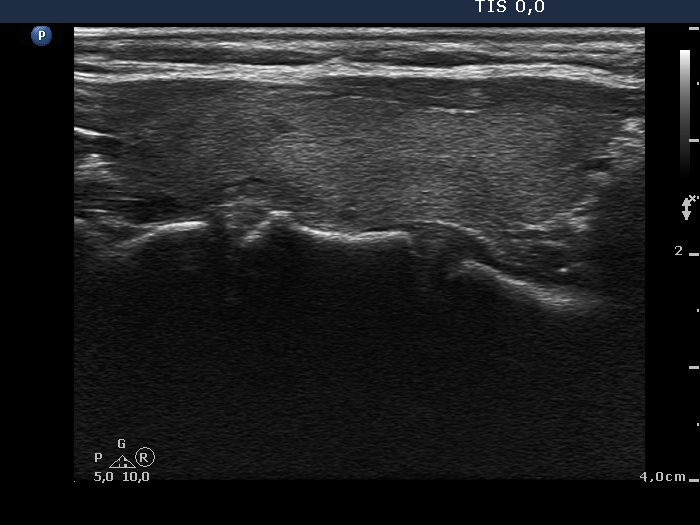

Subacute granulomatous thyroiditis - case 1777

Five months after the first examination (ultrasonographic picture 7)

Left lobe, longitudinal scan.